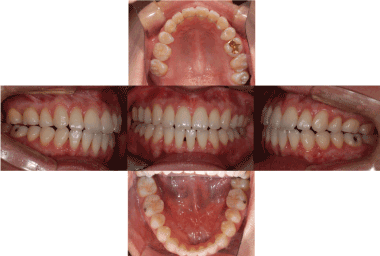

Before treatment, all six patients had ICR and an open bite caused by counterclockwise rotation of the mandible (Figure 4). The patients recovered a normal relationship in the anterior region via appropriate treatment of TMJ disorder accompanied by orthognathic surgery and orthodontic treatment. During follow-up, three patients intermittently complained of having symptoms of TMJ disorder. These symptoms were relieved by taking precautions and consulting their dentists, without the need for special treatment. One patient had a relapse of TMJ disorder due to a head injury and accordingly received an intra-articular injection of anti-adhesive agents. All six patients showed no signs of either a relapse of ICR or an open bite during radiographic and clinical examinations (Figure 5).

Figure 4. Initial intra-oral photo: Anterior open bite was observed